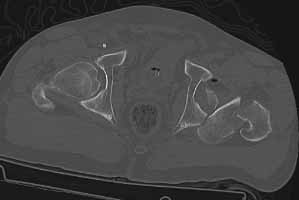

49 year old male, active speedskater, one year after MVC with multiple trauma and mild traumatic brain injury. Pipkin type IV fracture of the left hip. Same day ORIF through KL approach. No heterotopic ossification "prophylaxis". Day 7 wound revision for hematoma. Full weightbearing after 3 months. Full recovery except left hip function due to early severe HO. Function after one year: fixed ankylosis in 40 degrees flexion, 10 degrees exorotation. Patient frequently asks for attempt to improve hip function.

Post Op 1 year - Click to Magnify

Use the CT scan to direct your exposure for excision ... operate wherever the bone is ... sometimes it forms remote from your initial surgery site and demands a separate exposure.

A 3D CT helps define the margins and direct the exposure(s).